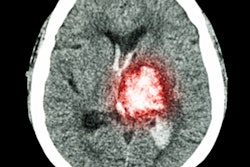

Patients with an ischemic stroke are showing up at hospitals and treatment centers more than two hours later than usual during the COVID-19 pandemic, according to a study published on May 28 in the Journal of NeuroInterventional Surgery.

The findings confirmed the suspicion that patients with stroke had been avoiding or delaying care, including a reported 40% drop in stroke scans. The delays are impacting the survival and recovery of patients, according to stroke surgeons from the Society of NeuroInterventional Surgery.